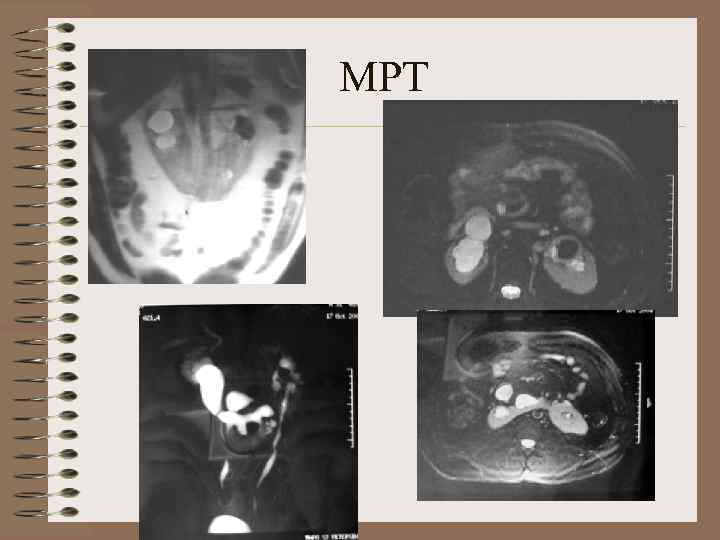

МРТ

МРТ. Сочетание юношеского поликистоза и подковообразной почки Т 1 Т 2

Поликистоз взрослых. МРТ Асимметрия объема изменений почек